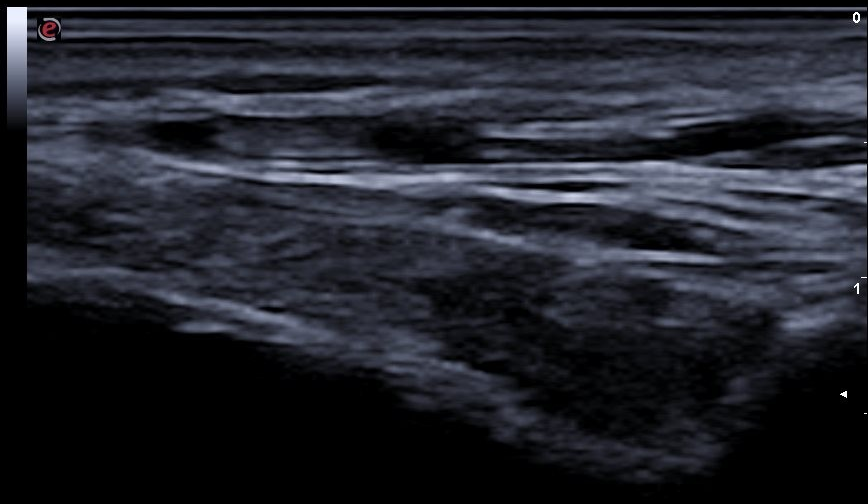

Descripción de los hallazgos ecográficos y las imágenes más relevantes para la resolución del caso

Signo del halo de manera parcheada. Se completa con realización de Doppler de las arterias temporales en ambos lados, observándose en porciones distales en el vaso una hipodensidad sin relleno y disminución del flujo compatible con inflamación del vaso. En tramos proximales se observa buen relleno vascular y flujo sin alteraciones. Todos estos hallazgos con compatibles con alta sospecha de arteritis de la temporal principalmente en sus tramos distales.